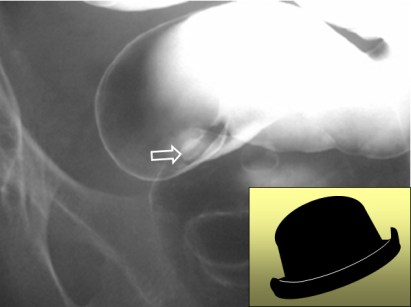

SIGNO DEL PSEUDOTUMOR DUODENAL

En la radiografía simple de abdomen, el bulbo duodenal lleno de líquido produce una imagen nodular o pseudotumoral, tal como vemos en la imagen (flecha). No debe confundirse con una litiasis biliar, que ocupa una posición similar pero que, cuando es visible, es porque tiene una densidad cálcica.

Este signo también se ha llamado Signo del pseudotumor del hipocondrio derecho.